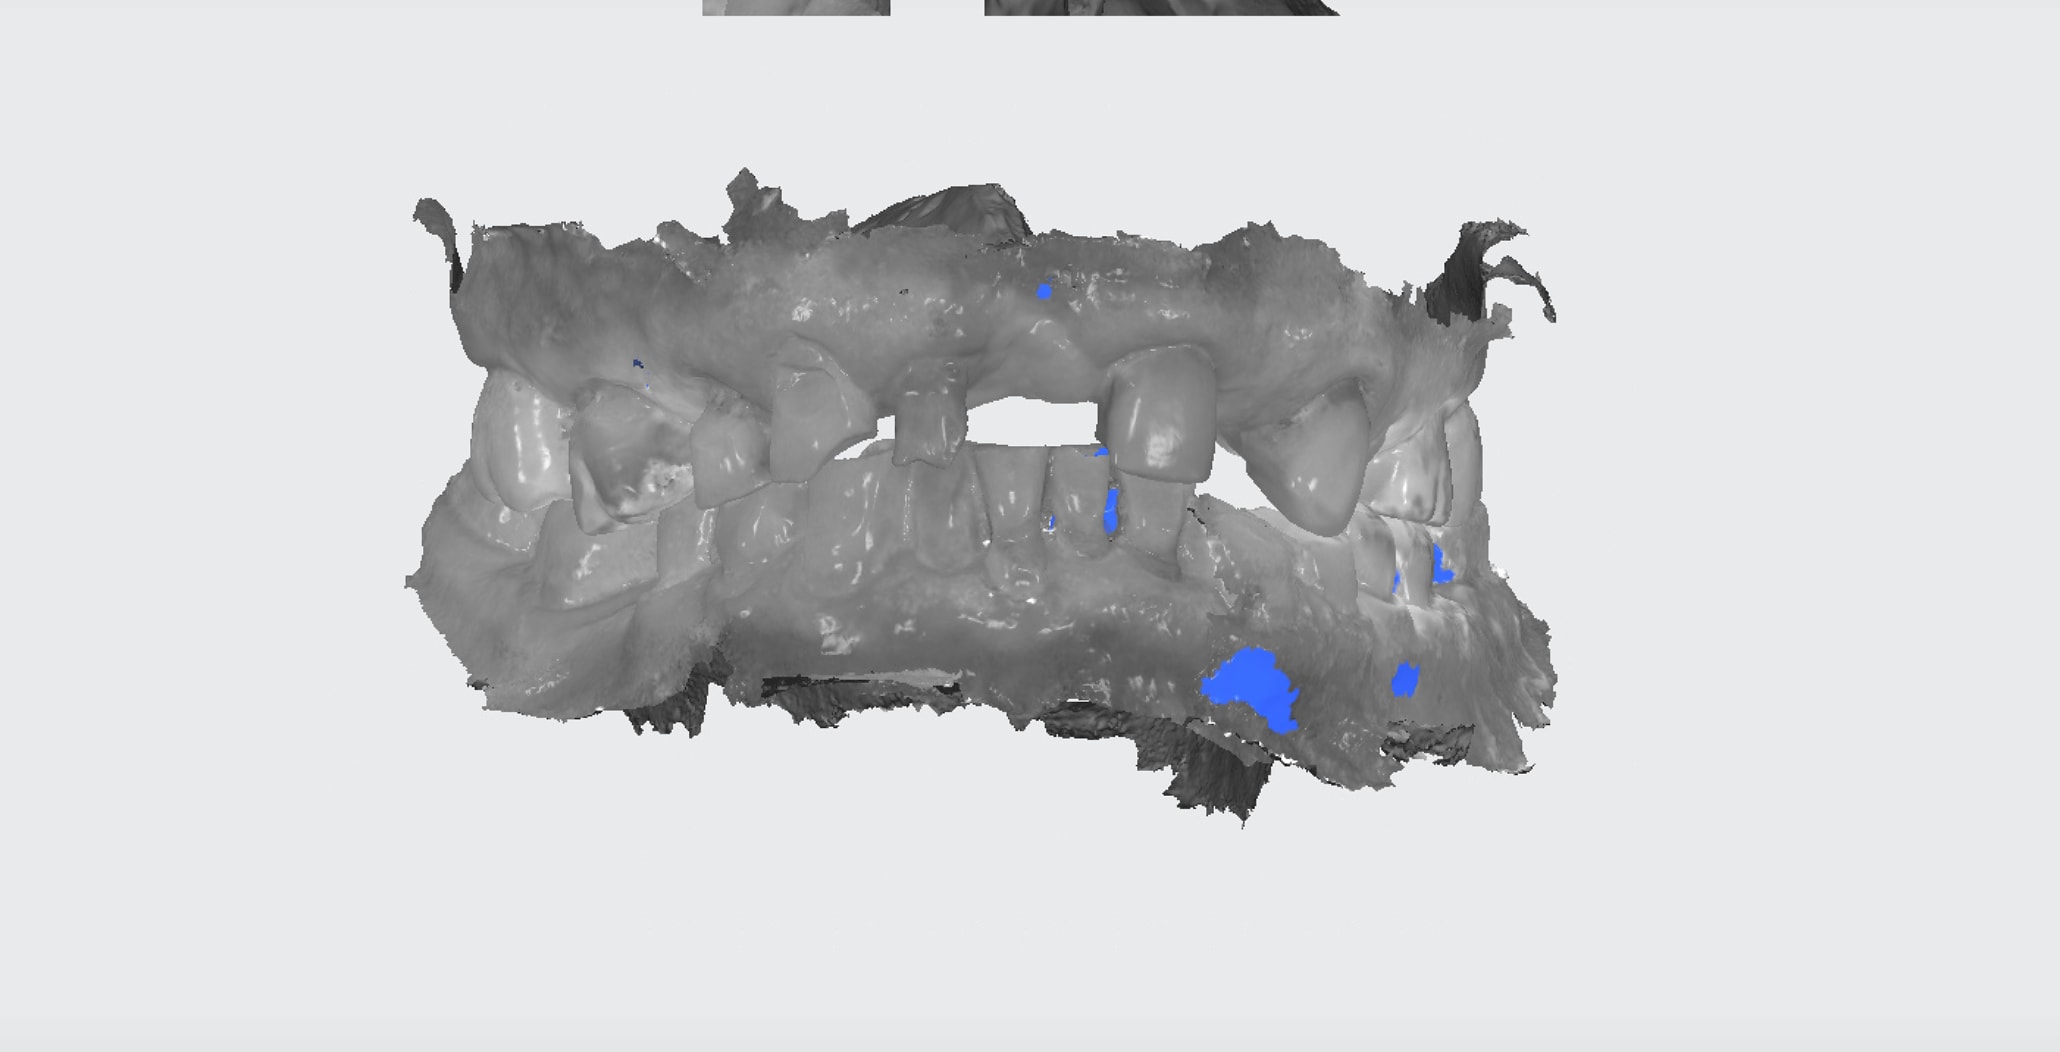

2 stellites one shot. Ca fait 8 mois que je fais des empreintes optiques et je ne suis toujours pas fier quand j'ai ce genre d'empreintes à faire.

Empreinte d'étude. En vue quelques cerams + stellite haut le tout one shot.

Pré prep ic cer 44 45 stellite one shot. Endo 45 réalisée . reste plus qu'à tailler. j'ai un doute pour 44 on va voir)